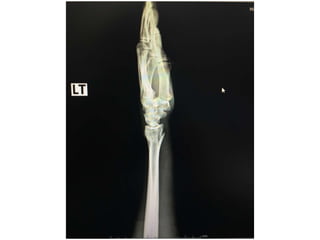

Film after on slab

Film X ray •Left wrist AP ,lateral